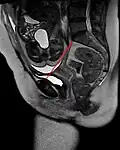

-

Pelvis -

Conjugata vera as measured on sagittal MRI -

Obstetric conjugate, as a measure of the pelvic inlet in the sagittal plane